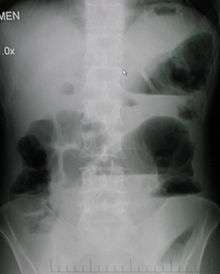

Upright abdominal X-ray demonstrating a small bowel obstruction. Note multiple air fluid levels.

Causes of small bowel obstruction include:[1]